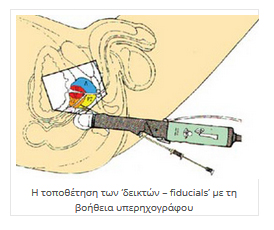

Η τοποθέτηση των "δεικτών αναφοράς" (κομμάτια σύρματος καθαρού χρυσού μήκους πέντε και πάχους 0,8 χιλιοστών (5 Χ 0,8 mm) εμφυτεύονται στον προστάτη με λεπτή βελόνα (18 G) υπό ενδορθική υπερηχογραφική καθοδήγηση.

Οι «δείκτες – fiducials» είναι τοποθετημένοι μέσα σε λεπτές ειδικές βελόνες (δεν διαφέρουν σε διάμετρο με αυτές των αιμοληψιών) και εμφυτεύονται στο προστάτη υπό καθοδήγηση διορθικού υπερηχογράφου από ειδικό Ουρολόγο ή Ακτινοθεραπευτή Ογκολόγο. Πριν εμφυτευτούν, γίνεται κάποια προετοιμασία του εντέρου, ίδια ή παρόμοια με αυτή που έγινε προ της βιοψίας.

ΠΡΟΕΤΟΙΜΑΣΙΑ ΤΟΥ ΑΣΘΕΝΟΥΣ

Για να γίνει η θεραπεία, πρέπει να υπάρχει σχετική ακινησία της περιοχής και εντοπισμός του στόχου. Για την ακινησία, γίνεται κατασκευή εξατομικευμένου αφρώδους στρώματος για μείωση των κινήσεων της πυέλου και των κάτω άκρων με διαδικασία αναίμακτη και μη επεμβατική. Για τον εντοπισμό του στόχου, χρειάζεται η τοποθέτηση "δεικτών" (fiducials – markers) μεγέθους 5 χιλ. μέσα στο προστάτη αδένα για να υπάρχει στόχευση με απόλυτη ακρίβεια. Η τοποθέτηση γίνεται με διορθικό υπερηχογράφημα και τοπική αναισθησία.